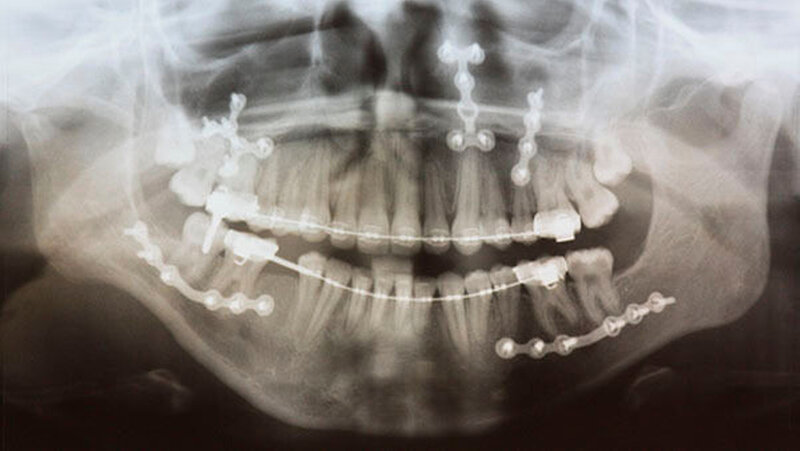

Daraufhin wurden eine kieferorthopädische Behandlung mit einer festsitzenden Spange und nacheinander zwei Operationen zur Umstellung des Ober- und Unterkiefers durchgeführt. Diese ersten Operationen konnten jedoch die weiter zunehmende Abweichung des Unterkiefers nach hinten und damit auch den offenen Biss nicht stoppen.

Mit der virtuellen Planung, individuellen Kiefergelenkprothesen und einer zusätzlichen Rückpositionierung des Oberkiefers in die ursprüngliche Lage erfolgte dann die Operation. Alles erfolgte in einem Operationsgang. Die Bonner MKG-Chirurgen fertigten die Endoprothesen für die Frau individuell im CAD-/CAM-Verfahren an. Dafür wurden die Daten der Computertomografie des Schädels zugrunde gelegt.

Durch diese hoch anspruchsvollen Verfahren ließ sich annähernd die ursprüngliche Position des Unterkiefers vor der Einschmelzung wiederherstellen; in der gleichen Operation wurde die Position des Oberkiefers der jetzt idealen Stellung des Unterkiefers angepasst.